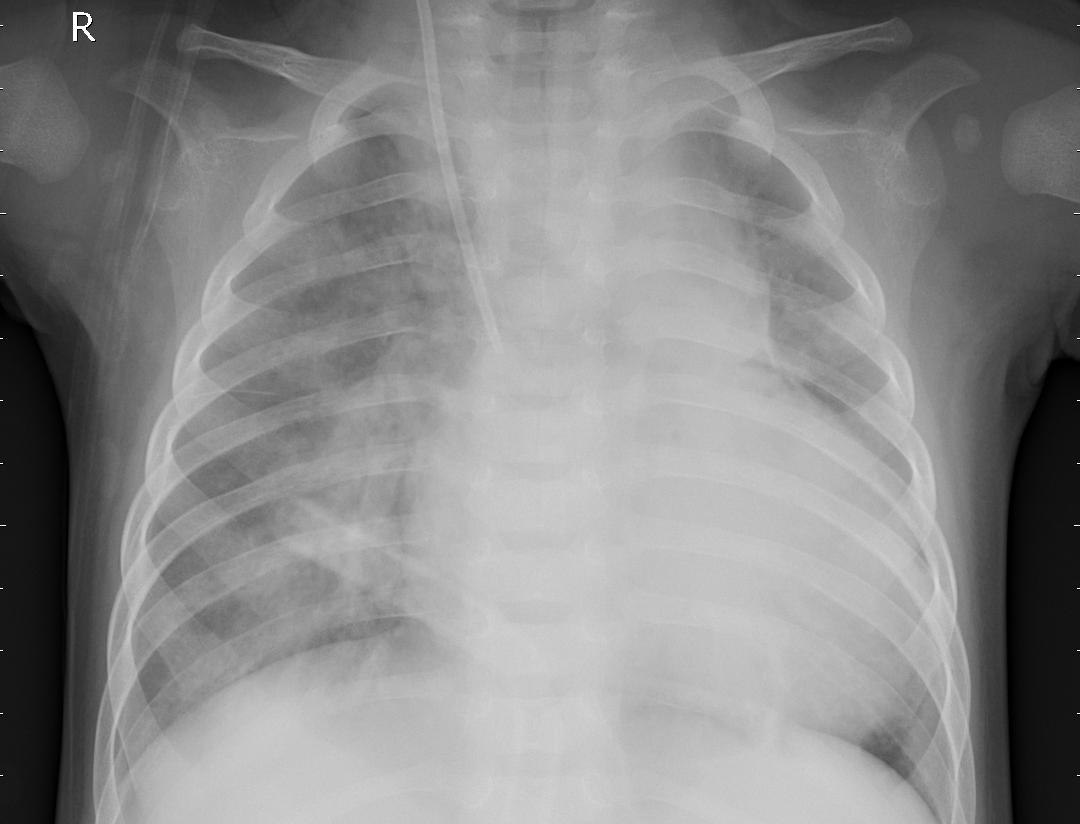

요약해보면 보자면 폐 속에 고름, 혈액 등이 차 있으면 X-ray 투과율이 떨어지며, 이로 인해 구름 같은 모양의 음영이 관찰된다면 폐렴이라 진단할 수 있다.

위의 두 사진을 비교해 보면 폐렴 환자의 X-ray는 정상에 비해 구름같은 음영이 관측된다.

이러한 현상은 폐 전체 혹은 일부에 나타날 수 있다.

[그림 1] dataset의 test/NORMAL/IM-0001-0001.jpeg

[그림 2] dataset의 test/PNEUMONIA/person113_bacteria_541.jpeg